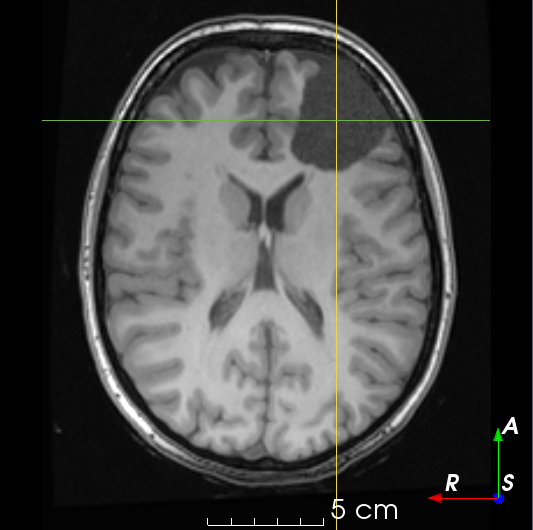

Refer to caption

(a)

(b)

(c)

(d)

(e)

(f)

Figure 3: Manual labels from Rater A (green) and Rater D, the model trained with PubFull + EpiPre + Pseudo (magenta). Errors caused by a (a) small resection, (b) blood clot in cavity and (c) brain shift; segmentations corresponding to the (d) 50th, (e) 75th and (f) 100th percentiles giving a DSC of 81.7, 86.5 and 93.8, respectively.